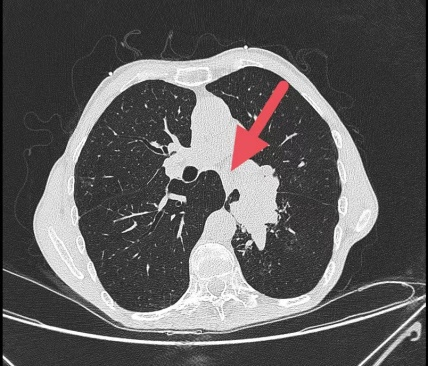

患者莫先生(化名)1个月前开始出现咳嗽、咳痰,并逐渐出现胸闷、憋气,走路时呼吸困难,且症状进行性加重。曾在多所医院就诊,但效果都不理想。经过朋友推荐,莫先生慕名前往自治区南溪山医院寻求帮助。在进行诊疗时,莫先生表现出轻微活动后即出现显著的呼吸困难,且在未吸氧状态下,其末梢血氧饱和度低于85%(正常范围应超过95%)。通过肺部CT扫描及支气管镜检查,发现其左侧主支气管被新生物阻塞,伴随有肺不张和严重的肺气肿,肺功能评估结果极差。

术前